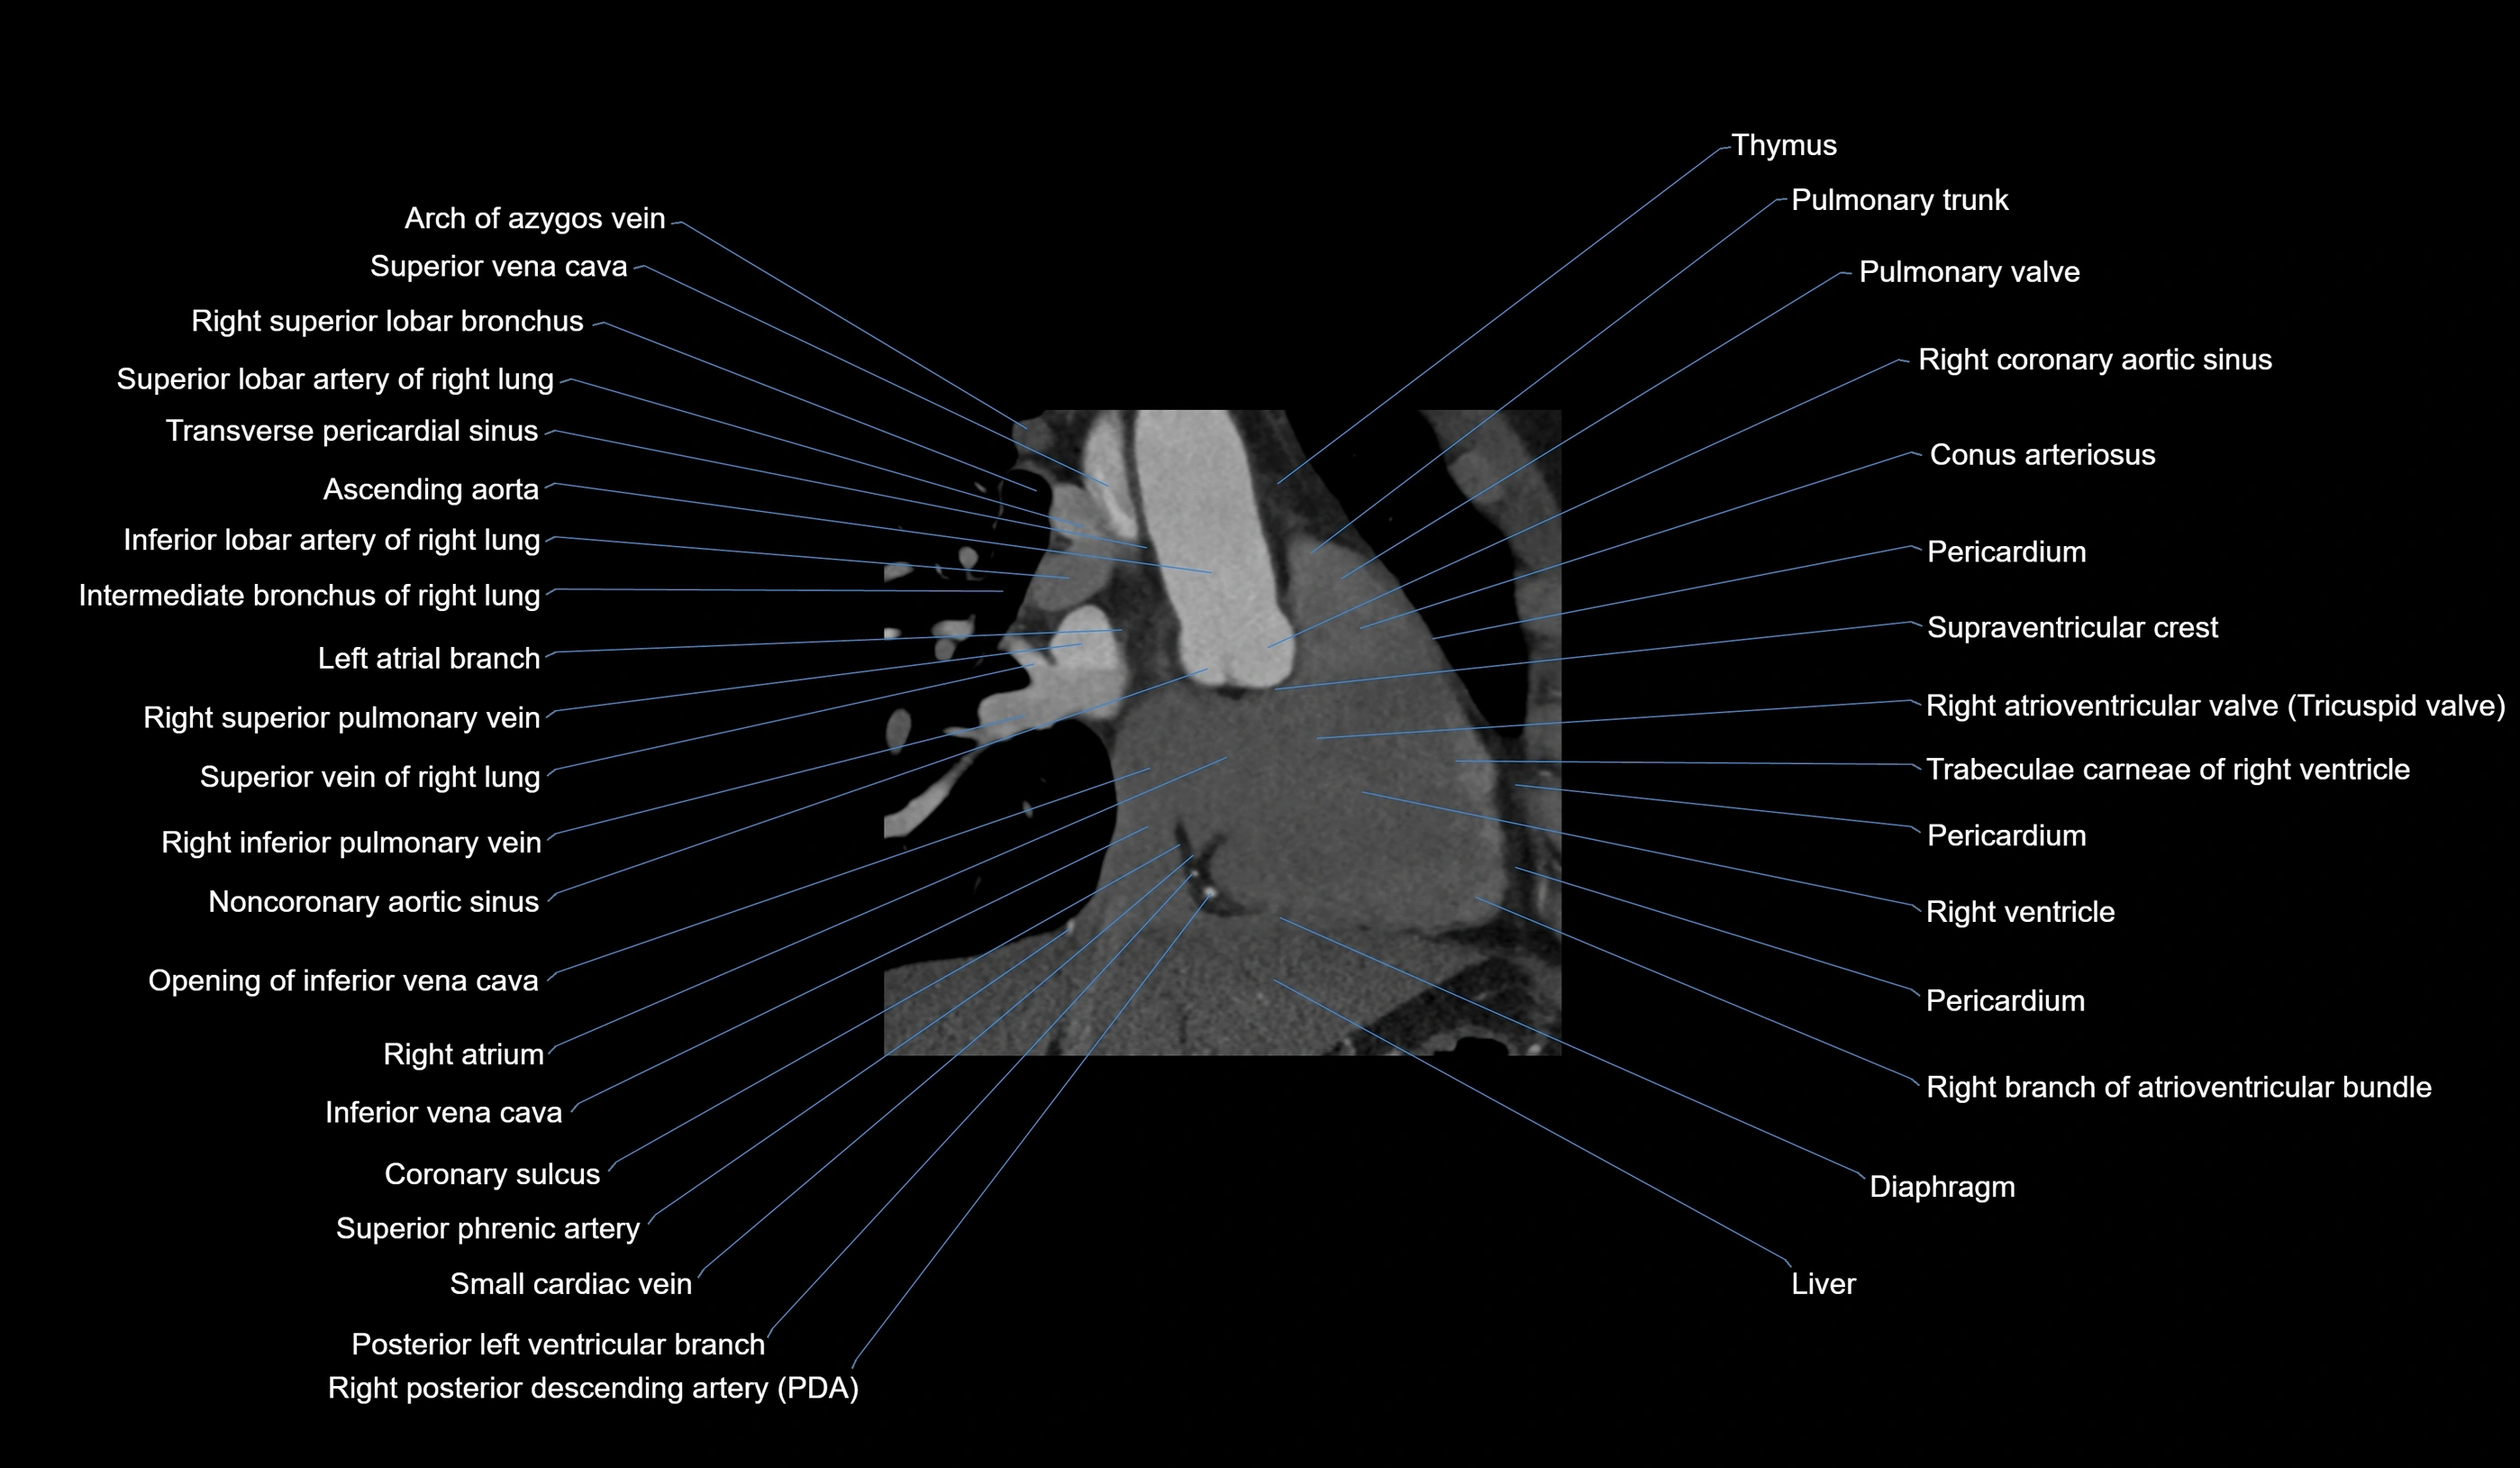

CT Appearance

Non-contrast CT (Calcium Scoring):

-

AM artery visualized for coronary calcium scoring

Calcified plaques appear as hyperdense foci; scored with Agatston method

CT Coronary Angiography (CCTA):

Best non-invasive modality for acute marginal artery visualization

Shows origin, course along the acute margin, and right ventricular branches

Detects stenosis, occlusion, calcified and non-calcified plaques, aneurysm, or anomalous course

Multiplanar reformats and 3D reconstructions help in pre-PCI and surgical planning

Critical for assessing right ventricular infarction risk in RCA disease

MRI image

CT images